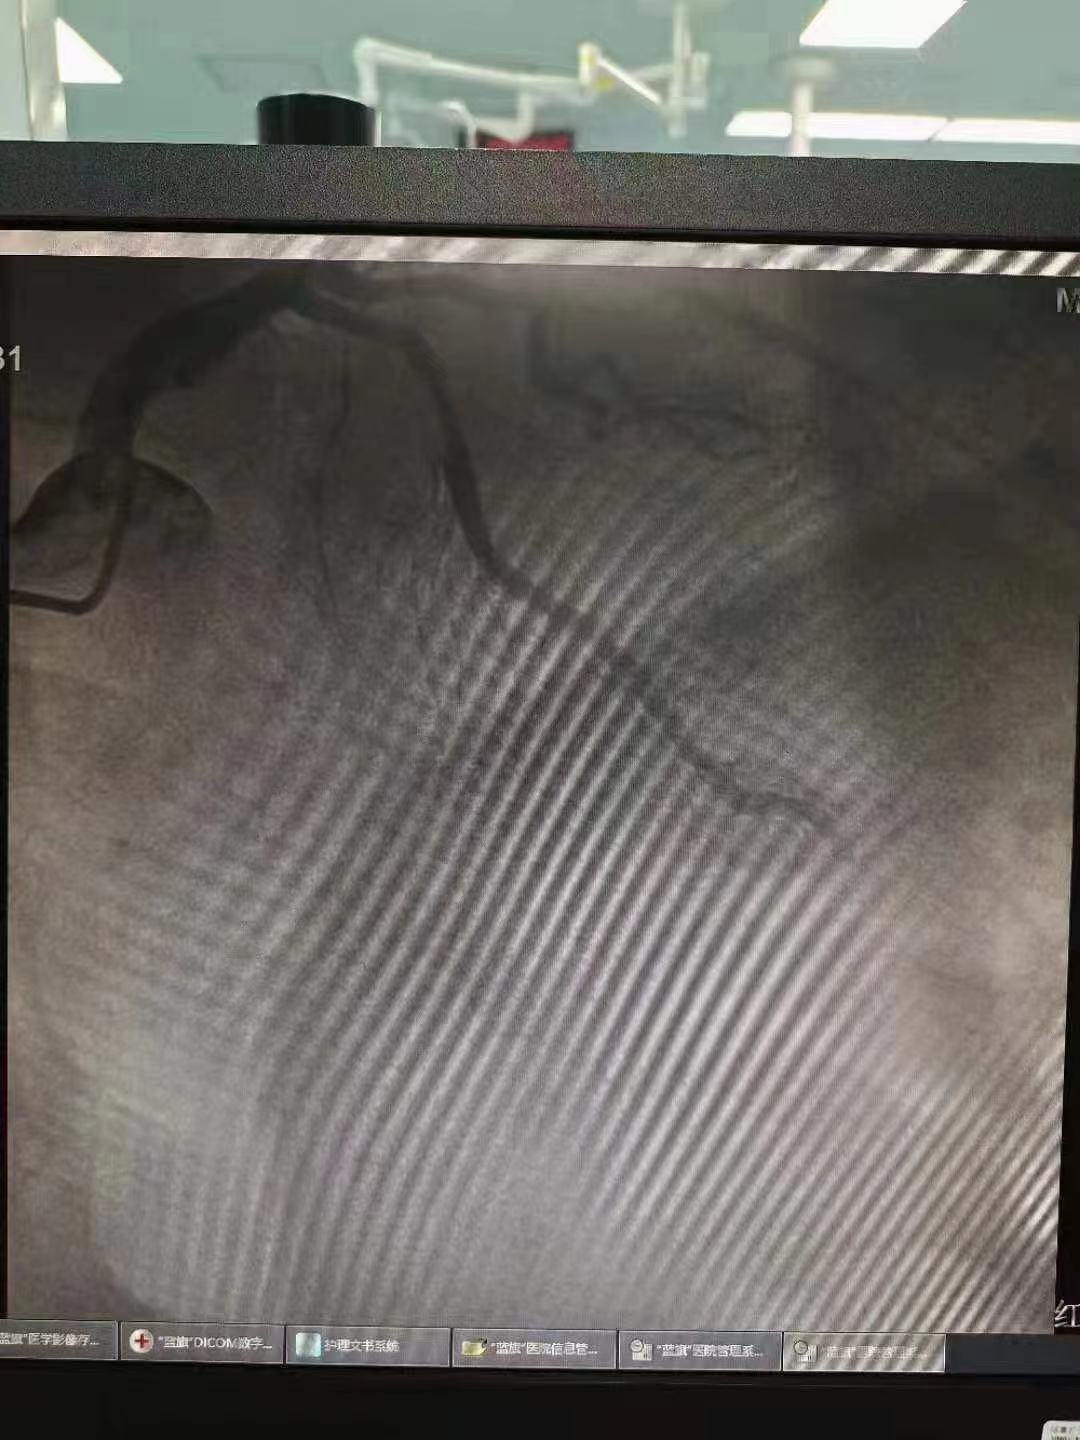

祝賀 云南省滇南中心醫(yī)院  黃銳團(tuán)隊(duì)成功為患者植入3.5~15Xinsorb生物可吸收支架!